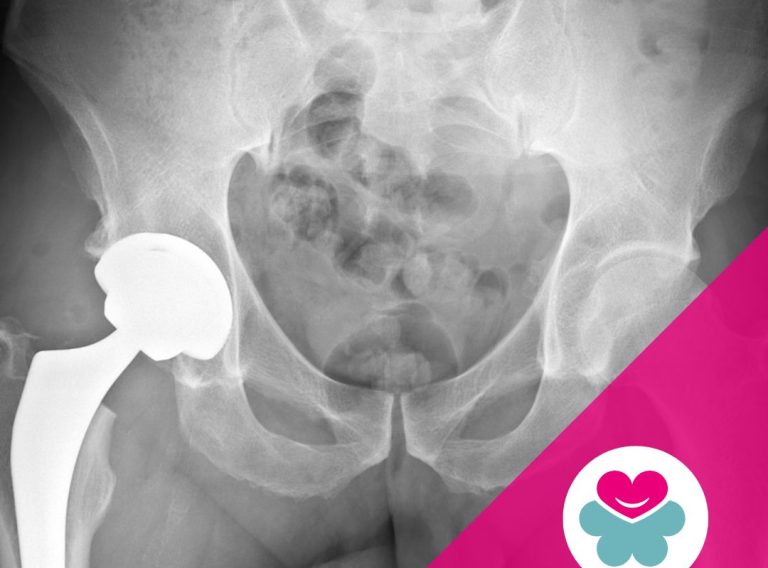

- Riabilitazione post-operatoria, per interventi chirurgici ortopedici o neurologici.